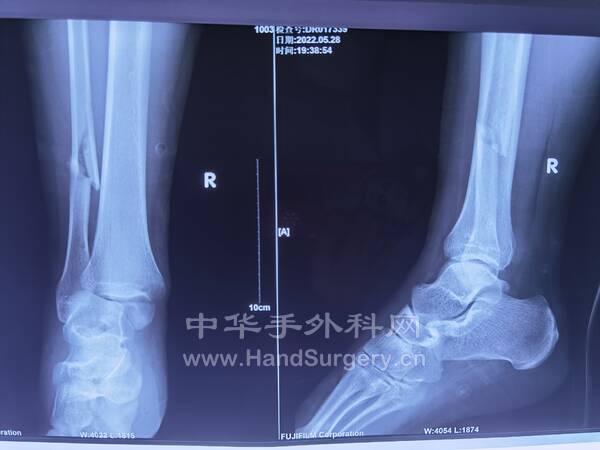

3.外院手术治疗1.5个月的患者,患者非常年轻!